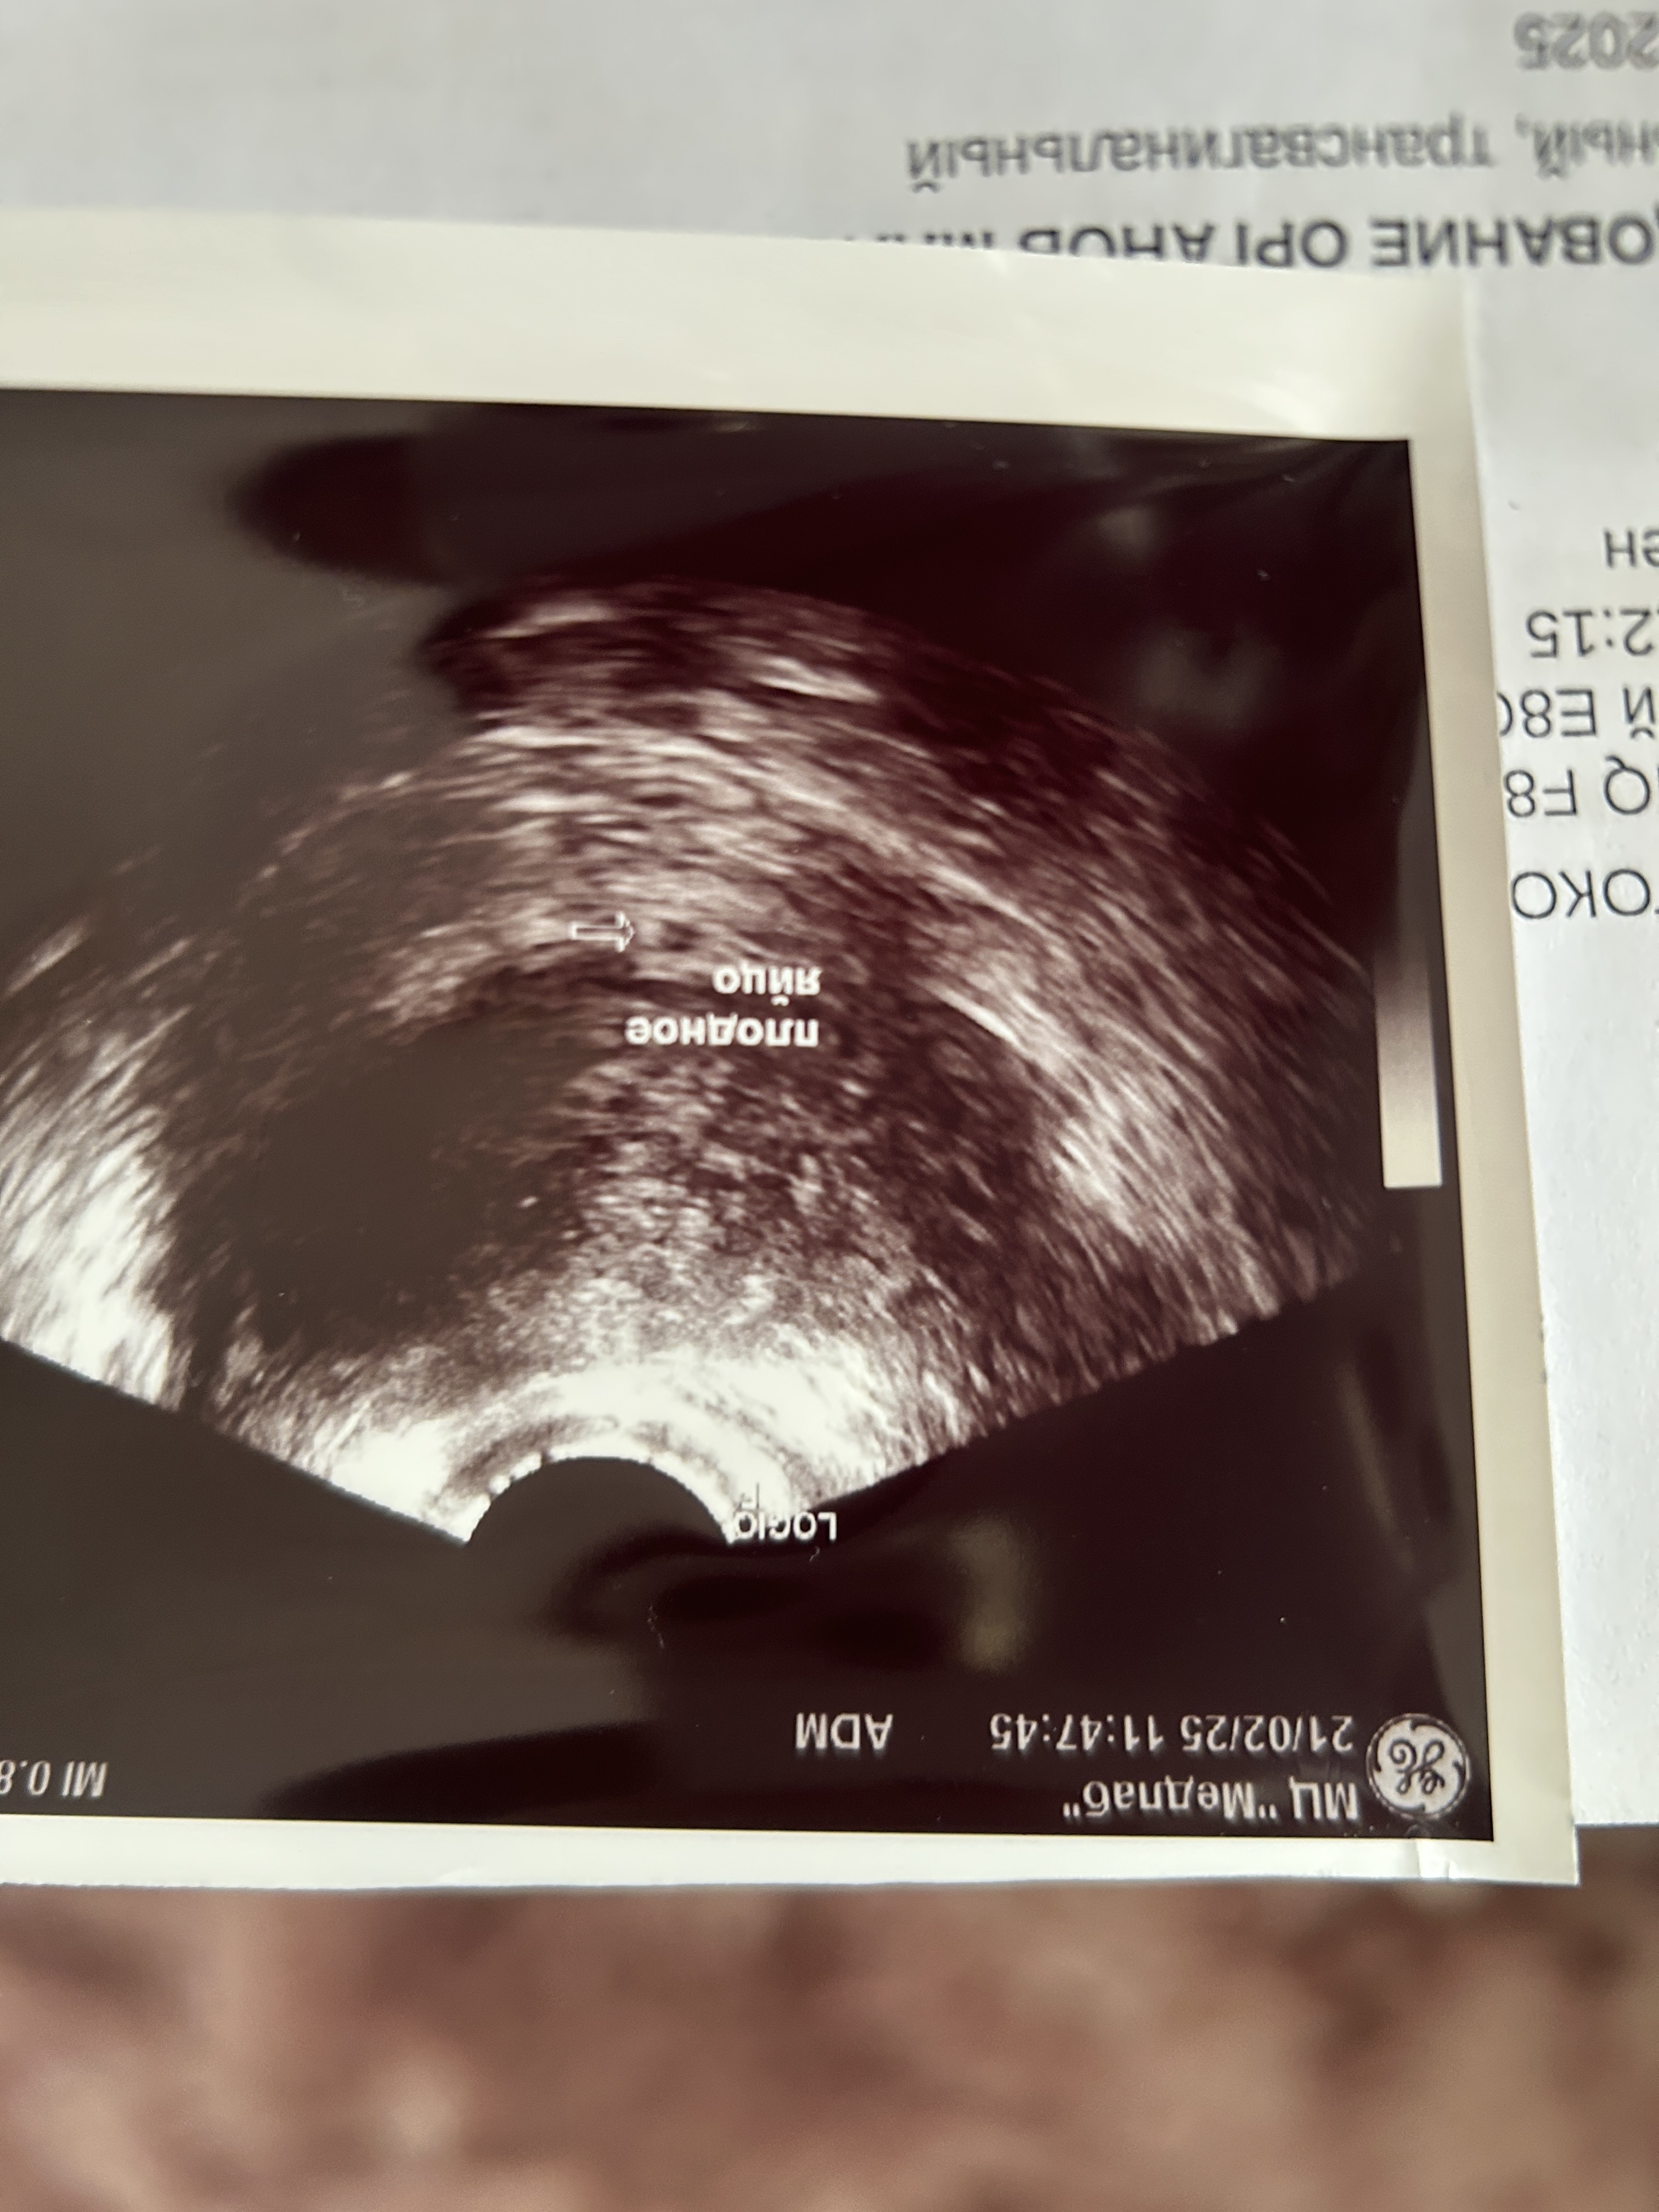

Алёна, ходила сегодня .Увидели только ПЯ и желточный мешочек .сказали придти через неделю 🙏🏻 хотела фото вам добавить) что то ни как .

Алёна, вот первое узи в 3 недели и второе Изображение Изображение